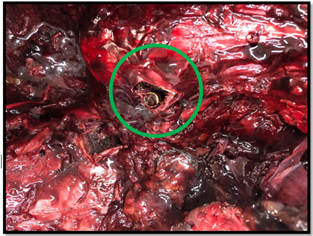

If it weren't for the existence of the X-Ray device, this projectile would be difficult to locate in the corpse. In the photograph to the right, the image that the Forensic Expert obtains during the autopsy examination is demonstrated. It is extremely difficult to search for the projectile amid the viscera of the corpse.

It is only with the aid of the X-Ray apparatus that it was possible to locate the projectile and extract it from inside the colon (circled in green in the photograph to the right).1–11